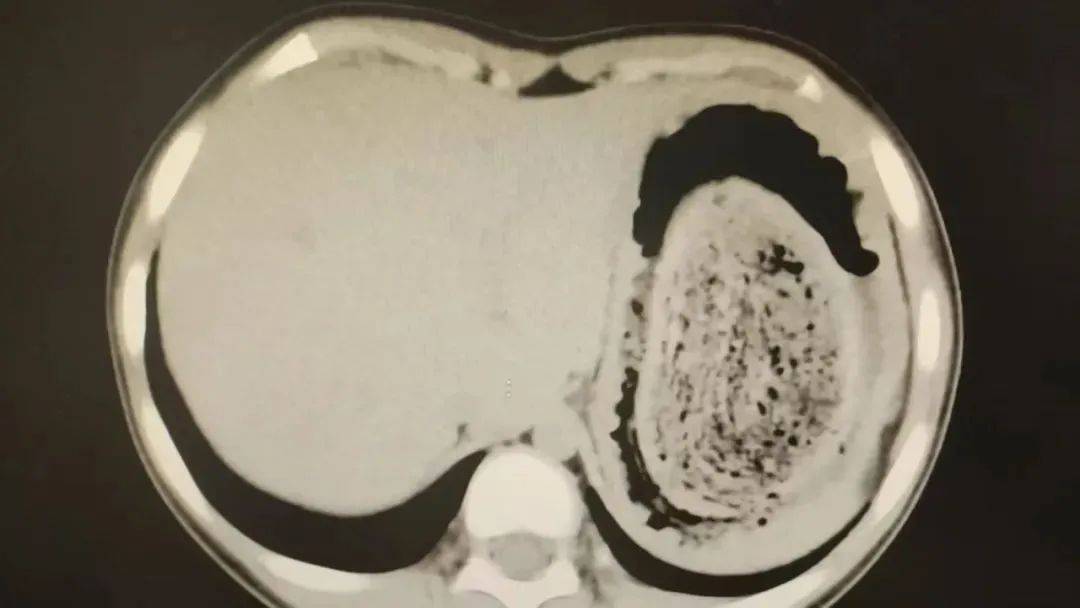

在胃镜帮助下,妮妮胃里的情况逐渐明了皇冠登3管理出租 。一个滚圆黑色的毛发球混合着食物残渣占据整个胃腔,这些头发相互缠绕形成一个实心的“发石”,此外胃里还有一个鸡蛋大小的溃疡。

10岁女孩园园(化名)因持续3天的上腹痛伴呕吐被紧急送医皇冠登3管理出租 。影像学检查结果显示,她的胃部存在一个巨大的团块状阴影,初步怀疑为异物堵塞。据家长回忆,园园从1年前开始就有偷偷吃头发的习惯,但家人并未重视,直到这次症状严重才意识到问题的严重性。